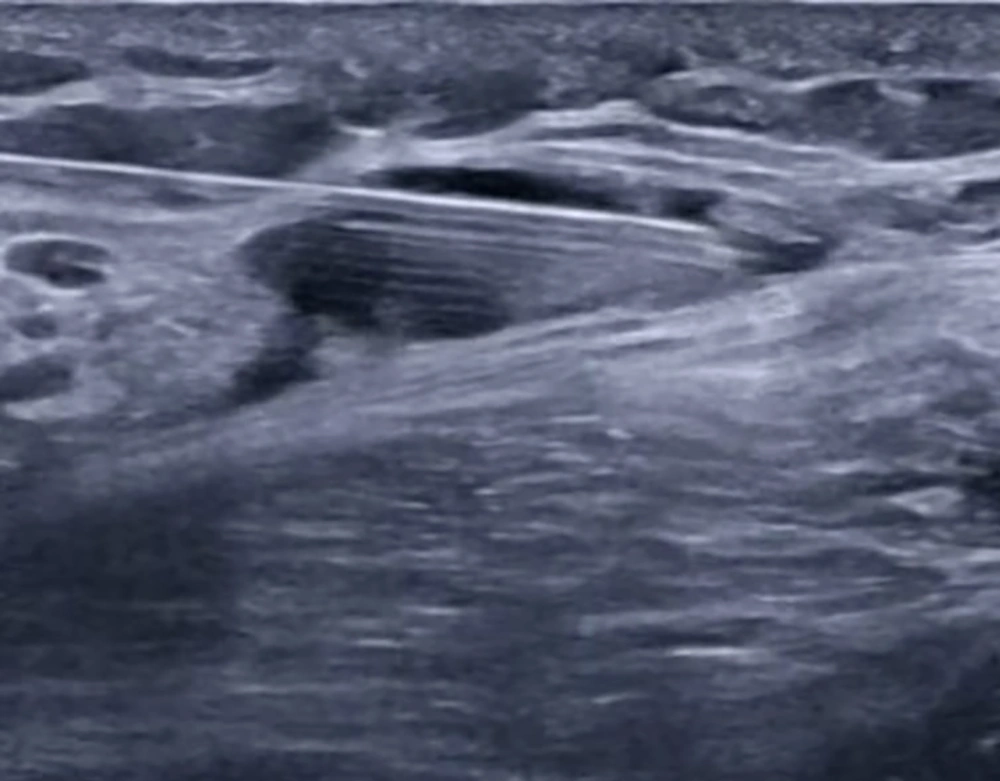

In group S, following completion of the SCPB, the SAP block was performed with the patient in the lateral decubitus position, operative side up, and the ipsilateral arm abducted to expose the midaxillary region (12). A high-frequency linear US probe (6 - 12 MHz) was positioned over the midaxillary line at the level of the 4th–5th ribs, identifying the latissimus dorsi (LD) muscle superficially and posteriorly, the serratus anterior (SA) muscle deep to LD, and the underlying ribs and pleura. Using an in-plane posterior-to-anterior approach, an 80-mm block needle was advanced under continuous US guidance into the fascial plane between the LD and SA muscles (superficial SAP). After confirming negative aspiration, 20 mL of 0.25% bupivacaine was injected incrementally, with hydrodissection confirming correct placement and real-time imaging verifying spread of local anesthetic along the plane in both cranial and caudal directions to ensure adequate coverage (Figure 3).